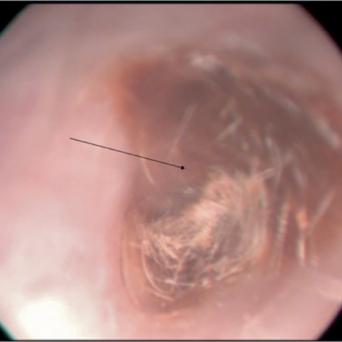

L’image

du jour

Illustration.